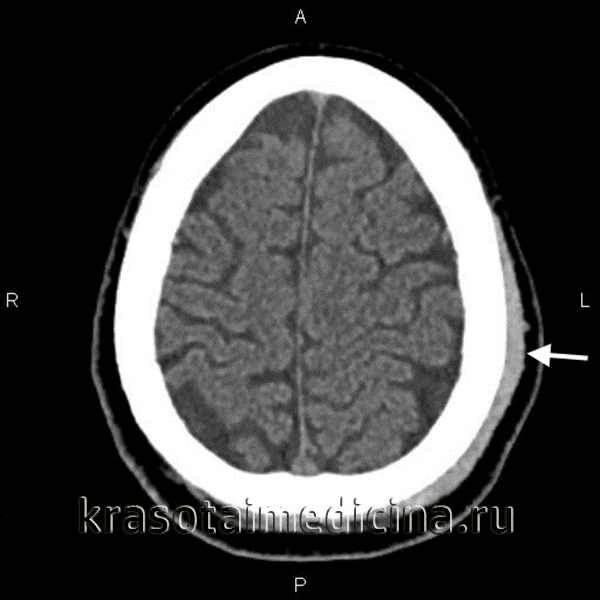

Добавлено: 18.04.2023, 01:56 Источник: Гематома мягких тканей – это полость, образовавшаяся в результате травмы и заполненная кровью или сгустками. Возникает при излитии крови в ткани из поврежденного сосуда. Представляет собой плотное или флуктуирующее опухолевидное образование, болезненное при пальпации, сопровождающееся отеком и изменением цвета кожи. При глубоком расположении проявляется нарушением формы и локальным увеличением объема пораженного участка. Патология диагностируется на основании жалоб, данных анамнеза и внешнего осмотра. В сомнительных случаях назначается ультрасонография. Лечение – местные консервативные мероприятия, в тяжелых случаях показано вскрытие, дренирование. ![]() О заболевании По размерам локальные кровоизлияния могут быть маленькими или обширными. В одних случаях они локализуются поверхностно – в подкожном или подслизистом слое. В других случаях – залегают в толще мышечного слоя или во внутренних полостях организма. Чем большее количество сосудов повреждено, тем тяжелее и обширнее гематома. Симптоматика локального кровоизлияния появляется практически сразу после травматического воздействия. Обычно первыми признаками являются ограниченный отек, интенсивные боли при надавливании и отсутствие флюктуационного симптома. Гематомы чаще всего образуются в местах, подверженных травматизации – голень, затылочная область головы (при падении назад), лицо (прямой удар). Спонтанные гематомы мягких тканей могут иметь разную локализацию и часто являются осложнением более интенсивной антикоагулянтной терапии. Диагностика в большинстве случаев не вызывает сложностей и основана на визуальной оценке поврежденной области. При глубоком залегании гематомы проводится визуализирующая диагностика – ультразвуковая, рентгенологическая или магнитно-резонансная. Лечение в большинстве случаев осуществляется консервативным способом. Хирургическое вмешательство может потребоваться только при больших гематомах с продолжающимся кровотечением. Почему гематома меняет цвет Медики выделяют три отдельные стадии гематомы, через которые она должна пройти, прежде чем полностью исчезнуть. Каждая из них характеризуется определенным цветом кожи, сквозь которую просвечивает кровоизлияние. Появление синяка. Сразу после ушиба мягких тканей ощущается резкая боль, участок кожи в поврежденном месте становится багрово-красным и напухает из-за отека тканей, затем красный цвет постепенно сменяется синим. Красный цвет придают эритроциты, содержащие большое количество гемоглобина. Спустя несколько часов гемоглобин начинает разрушаться, и место ушиба синеет. Из-за отека и воспаления ткани в поврежденном месте повышается температура. Позеленение. Спустя два-три дня отек и температура уменьшаются, состояние тканей более-менее нормализуется, однако сохраняются незначительные болевые ощущения при надавливании. Синий оттенок кожи понемногу переходит в зеленоватый цвет. Пожелтение. Примерно к пятому дню отек полностью проходит, остатки гемоглобина распадаются и выводятся из тканей. Место ушиба становится желтоватым, затем приобретает обычный цвет. Визуальные симптомы гематом наиболее хорошо заметны в случаях, когда излияние крови происходит в подкожном слое. Если же сгусток образуется в более глубоких слоях мягких тканей, то снаружи заметна лишь небольшая, но болезненная припухлость. Такие образования намного более опасны, поскольку процесс протекает незаметно и может сопровождаться осложнениями. Виды повреждений Чем быстрее образуется гематома, тем тяжелее протекает выздоровление. Травмы этого рода подразделяют на: - легкие, развивающиеся в течение суток, сопровождающиеся слабыми болезненными ощущениями и не требующим специального лечения; - средней тяжести, для появления которых требуется не более 5-6 часов, сопровождающиеся заметной припухлостью и болью, ухудшающие двигательную функцию конечности; - тяжелые, образующиеся в течение 2 часов после ушиба, сопровождающиеся нарушением функций конечности, острой болью и заметной припухлостью. Лечение гематом среднего и тяжелого типа должно проводиться под наблюдением врача, чтобы исключить возможные негативные последствия травмы. Кроме тяжести повреждения, существуют и другие критерии классификации гематом: - по глубине расположения – под кожей, под слизистой оболочкой, в толще мышечной ткани, под фасцией и т.д.; - по состоянию разлитой крови – несвернувшиеся (свежие), свернувшиеся и лизированные (заполненные старой кровью, которая не способна к свертыванию); - по характеру распространения крови – диффузные (кровь пропитывает ткань и быстро распространяется), полостные (кровь скапливается в полости между тканями) и осумкованные (с течением времени полость, заполненная кровью, окружается «сумкой» из соединительной ткани); - по состоянию сосуда – пульсирующие (кровь свободно выливается из сосуда и втекает обратно) и непульсирующие (разрыв сосуда быстро запечатывается тромбом). Классификация Систематизация осуществляется по нескольким признакам. Целью деления на группы является оценка тяжести патологии, выбор лечебной тактики, определение необходимости проведения хирургического вмешательства и наиболее вероятного прогноза. В клинической практике различают следующие виды гематом: По локализации. Гематомы могут быть расположены под кожей, в подслизистом слое, под фасцией, в толще мышечной ткани. Наиболее крупные полости локализуются внутри мышц или подфасциально (между мышцей и фасцией), что обусловлено богатым кровоснабжением и эластичностью скелетной мускулатуры. По состоянию сосуда. Пульсирующие гематомы формируются при повреждении сосуда большого калибра, отличаются отсутствием тромба в зоне повреждения, возможностью свободного движения крови из полости образования в полость сосуда и обратно. Непульсирующие гематомы обнаруживаются при нарушении целостности мелких и средних сосудов, дефект стенки которых быстро закрывается тромбом. По состоянию излившейся крови. Несвернувшиеся (свежие) гематомы выявляются в первые часы или дни после травмы, свернувшиеся – спустя несколько суток, лизированные (заполненные старой кровью, неспособной к свертыванию) – через несколько недель. Указанные сроки могут колебаться в зависимости от активности факторов свертывания, размера образования и иных обстоятельств. При проникновении инфекции наблюдается инфицирование, позже – нагноение. По отношению к тканям. При развитии диффузных гематом процесс пропитывания тканей кровью преобладает над процессом их «раздвигания», полость небольшая или отсутствует. При формировании ограниченных образований ткани пропитаны незначительно, основная масса излившейся крови находится в полости. Осумкованные гематомы определяются в отдаленные сроки, характеризуются наличием слоя плотной соединительной ткани, отделяющей полость от окружающих структур. По степени тяжести. Легкие гематомы возникают примерно через сутки после травматического эксцесса, чаще рассасываются самостоятельно. Образования средней тяжести формируются в течение 3-5 часов, требуют проведения консервативных или оперативных мероприятий. Тяжелые повреждения диагностируются через 1-2 часа после травмы, являются показанием для вскрытия и дренирования. ![]() КТ ОГК. Гиперденсное скопление крови в толще мышечного массива грудной стенки справа, окруженное зоной отека. Симптомы Первыми проявлениями патологии становятся боль и местный отек. Характерным отличием гематомы от других травм мягких тканей на ранней стадии является более выраженная ограниченность припухлости, отсутствие постепенного перехода от отечных структур к неизмененным. В последующие часы отек начинает распространяться. Болезненность усиливается, движения ограничиваются из-за боли. Пациенты предъявляют жалобы на ощущение давления или напряжения в пораженной зоне. При поверхностном расположении гематомы кожа становится синюшно-багровой. При глубокой локализации полости может выявляться локальная гиперемия кожных покровов, иногда цвет кожи не изменяется. При пальпации на начальном этапе флуктуация обычно отсутствует, определяется уплотнение и резкая болезненность. После формирования ограниченной полости, содержащей жидкую кровь, выявляется положительный симптом зыбления. Вначале пораженная область при ощупывании напряженная, после спадания отека плотность тканей может снижаться. При благоприятном течении припухлость постепенно уменьшается в размере и исчезает, при неблагоприятном – сохраняется в течение длительного времени, вызывает болезненность при движениях. Диагностика Диагностика осуществляется врачом-травматологом. При отсутствии признаков поражения костей и суставов дополнительные исследования обычно не требуются, диагноз выставляется с учетом данных анамнеза (наличие свежей травмы с характерным механизмом), жалоб больного и результатов физикального обследования. При глубоко расположенных гематомах для оценки тяжести повреждения и дифференцировки с ушибом может назначаться УЗИ мягких тканей. При сопутствующем поражении твердых структур выполняется рентгенография соответствующего сегмента. Кроме ушиба дифференциальную диагностику иногда приходится проводить с переломами, надрывами связок и мышц, реже – с синдромом позиционного сдавления, острым миозитом, ишемией при тромбозе сосуда мелкого или среднего калибра и некоторыми другими состояниями, сопровождающимися плотным локальным отеком. ![]() КТ головного мозга. Гематома периферических мягких тканей левой теменной области Лечение гематомы мягких тканей Лечение обычно осуществляется амбулаторно, тактика определяется тяжестью процесса и временем с момента травмы. При свежих повреждениях конечности придают возвышенное положение, прикладывают холод (грелку с холодной водой, пакеты со льдом, завернутые в полотенце), накладывают давящую повязку для уменьшения кровотечения. После организации небольших образований назначают УВЧ, применяют теплые грелки для ускорения рассасывания. Небольшие поверхностно расположенные гематомы вскрывают в условиях травмпункта. При крупных и глубоких полостях, появлении признаков инфицирования показана госпитализация в травматологическое отделение, вскрытие и дренирование на фоне антибиотикотерапии. При неинфицированных гематомах после вскрытия рекомендовано тугое бинтование для устранения полости и ускорения заживления. Видео про Гематома: откуда берутся ретрохориальные гематомы |